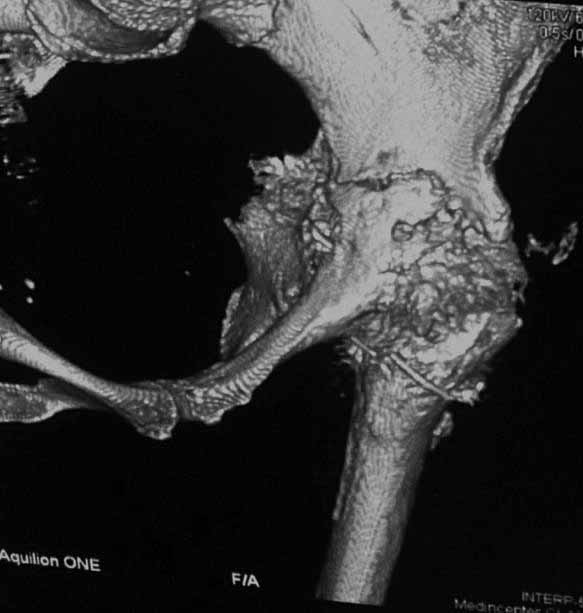

Уважаемые коллеги. Хотелось бы услышать мнения и советы по представляемому случаю.

Пациентка 45 лет. Бесцементное эндопротезирование левого тазобедренного сустава 6 лет

назад (впадина RM, Mathys, металл-металл, ножка Зульцеровская). За 10 лет до

протезирования коррегирующая остеотомия бедренной кости, которая не срослась в течение

года до удаления пластины, а затем срослась в течение 3 месяцев иммобилизации в кокситной

повязке. После протезирования получилось наблюдать пациентку почти постоянно, поскольку

через 2 года синтезировал ей лодыжки на оперированной стороне, затем, через несколько

месяцев удалил фиксаторы, а в 2009г. резецировал мениск на противоположной стороне. Боли

все эти годы не беспокоили. Пациентка чуть выше среднего роста, вес тела нормальный.

Физические нагрузки переносила хорошо. Работает на 7 этаже без лифта. Год назад экстирпация

матки по поводу лейомиомы больших размеров. Несколько месяцев назад появились боли в

области левого тазобедренного сустава. При рентгеновском и КТ исследованиях (июль с.г.)

нестабильность тазового компонента. От предложенной замены протеза пациентка на тот

момент, слава богу, отказалась. Через какое то время боли в области левого тазобедренного

сустава практически полностью прошли, а около 2 месяцев назад появилось ощущение

патологической подвижности таза и боли в паху справа, которые через некоторое время

уменьшились, а потом снова усилились после значительных физических нагрузок (много ходила

по песку на пляже, носила тяжести). Ежедневно принимала диклофенак. На рентгенограммах

переломы правой лонной кости. Сейчас госпитализирована из-за болей в паху справа. Боли

слева не беспокоят. На фоне снижения нагрузок в стационаре боли значимо уменьшились.

-Если думать о ревизии, то когда? На представленных снимках тазобедренный сустав до и

сразу после операции, затем 2 снимка 2009г., когда ничего не беспокоило, затем КТ 2-х

месячной давности и вчерашние рентгенограммы обоих тазобедренных суставов.